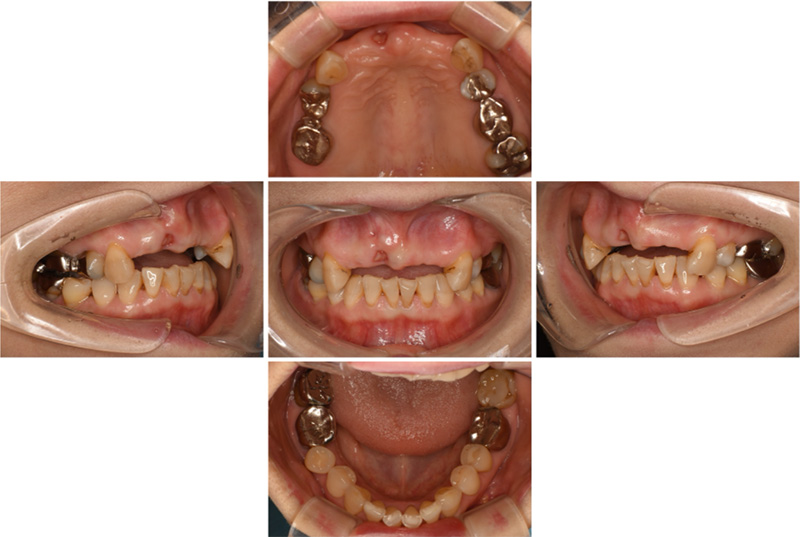

57歳男性

治療前